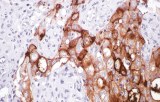

L’immunoistochimica (IHC) con anticorpi primari CE/IVD è essenziale per una diagnosi e classificazione accurata sia delle malignità ginecologiche che mammarie. Questi anticorpi consentono la rilevazione precisa di marcatori tumorali e proteine cellulari, supportando la diagnosi differenziale e guidando strategie terapeutiche personalizzate.

Gli anticorpi primari contro il recettore degli estrogeni (ER), recettore del progesterone (PR), HER2 e Ki-67 rimangono il pilastro della classificazione e delle decisioni terapeutiche nel cancro al seno. Questi anticorpi sono validati clinicamente e marcati CE/IVD per garantire una rilevazione affidabile e riproducibile dei biomarcatori – cruciale per guidare la terapia ormonale e le strategie di trattamento mirato.